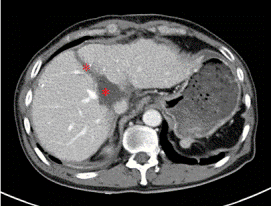

通过CT、磁共振以及三维重建的图像来看,王先生的肿瘤位于肝脏尾状叶,除左侧可见少量肝组织以外,肿瘤已侵犯绝大部分的尾状叶!“跟土豆差不多大!”胡伟表示,王先生的肝脏肿瘤约有5*5*4㎝大小,手术切除对于他来说是目前唯一有效的治疗方案!

术前增强CT显示肿瘤位于肝脏尾状叶